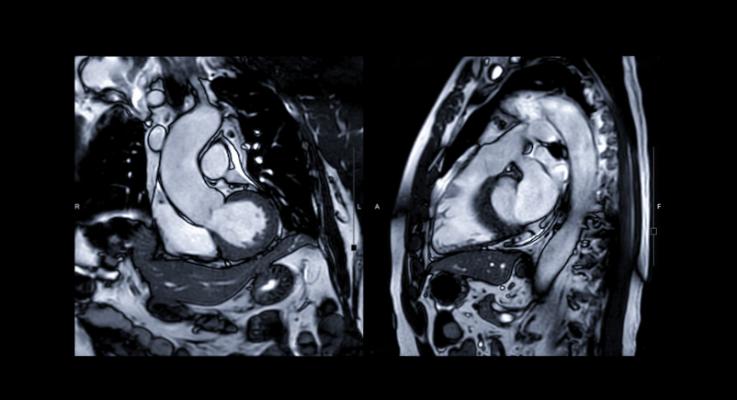

The research, published in the top science journal Advanced Science, found that injection of the trace mineral manganese could enhance MRI scans so that they provided more accurate details of heart function than traditional MRI methods.

Patrizia Camelliti, M.D., Principal Investigator and Senior Lecturer in Cardiovascular Science at the University of Surrey, said: "Magnetic resonance imaging (MRI) is increasingly used to diagnose and give information on heart conditions. This research using mice allows us to measure the health status of the heart muscle rapidly after a heart attack and could provide important information for optimising treatments in patients."